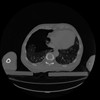

34 CUERPO,CE,Vol,1.0,CUERPO,,